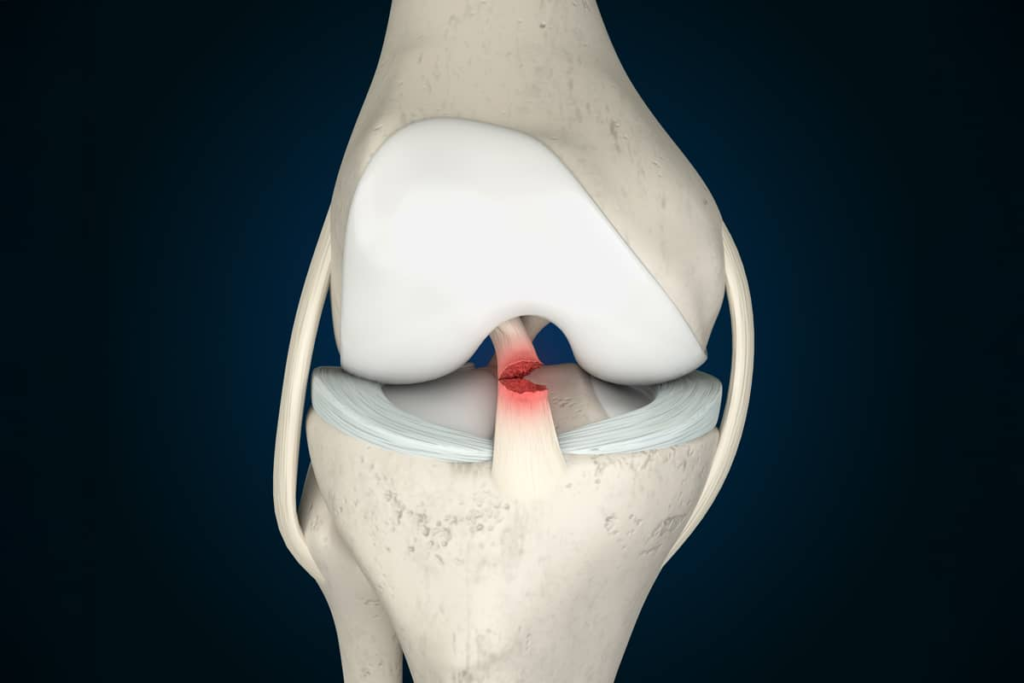

Ligament reconstruction is commonly recommended for injuries such as ACL tears, PCL injuries, MCL damage, LCL tears, and multi-ligament instability. These issues often occur due to sports injuries, sudden twists, accidents, or repetitive strain. The procedure involves replacing the torn ligament with a graft to restore natural stability and strength to the joint.